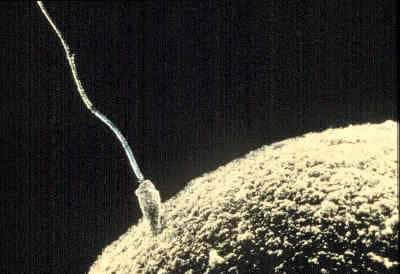

Chaque gamète mâle doit lutter pour arriver à l'ovule. © DR

Pour rejoindre l'ovule, le spermatozoïde le plus chanceux des 250 millions lancés à chaque course, doit emprunter des rapides, gravir des montagnes et nager jusqu'à lui.

Pour atteindre sa destination finale, il devra survivre aux attaques acidesacides des sécrétions vaginales malgré la protection du liquide séminalliquide séminal. Il lui faudra ensuite parcourir le col de l'utéruscol de l'utérus, la cavité utérine et enfin, pour les plus performants, la trompe utérine.

Malheureusement, trompe gauche ou droite, il faut choisir et 50 % des gamètesgamètes mâles se retrouvent dans une trompe sans ovule. Parmi les millions de spermatozoïdes dans la course, seuls quelques centaines traverseront la trompe.